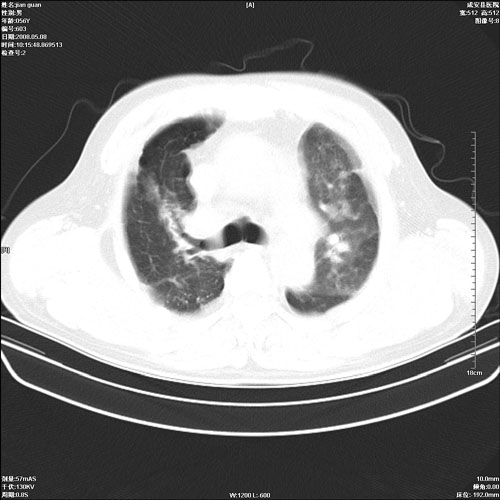

病人 男 60岁 主诉 胸闷 无明显发热 一般情况尚可。

肺结核?

两上肺陈旧性结核;慢支肺气肿、伴感染?

1.右上肺陈旧性肺结核.

两上肺陈旧性结核;慢支肺气肿

1.两上肺陈旧性结核;慢支肺气肿。

考虑.两上肺陈旧性结核;慢支肺气肿。肺心病

两上肺陈旧性结核,慢支肺气肿。

两上肺陈旧性结核;慢支肺气肿。肺肺间质纤维化

两上肺陈旧性结核;慢支肺气肿。

1.陈旧肺结核;

2.慢支肺气肿;

3.肺心病.